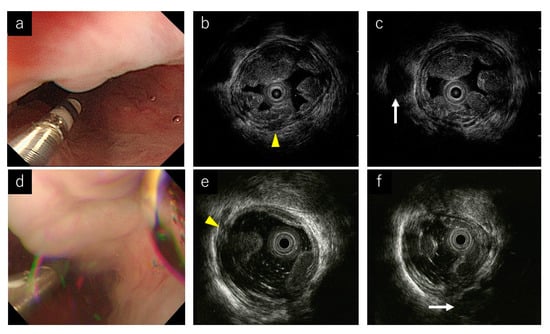

- Miyamoto, S.; Takahashi, K.; Ohya, T.R. New method of esophageal endoscopic ultrasonography with injected gel: Endoscopic ultrasonography-gel filling method. Dig. Endosc 2021, 33, e49–e50. [Google Scholar] [CrossRef]